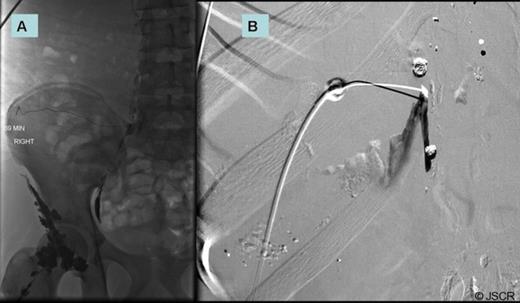

A few days later, the interventional radiologists attempted lymphangiography and embolization of the leaking duct (Figure 5). This also proved unsuccessful and did not improve the output. The patient was subsequently taken to the operating room for a re-exploration and attempted ligation of the lymphatic leak transabdominally. During surgery, the right crus was divided and the retroperitoneal tissues to the right of the supraceliac aorta were ligated in an attempt to obstruct the lymphatics draining proximal to the transhepatic injury. Following this operation, there was an immediate decrease in the output from the chest tube associated with an improved chest x-ray. The chest tube was removed on post-op day #7 once the patient tolerated a regular diet without any increase or change in output. The patient was discharged home the next day and has since recovered well from his injury.

Lymphangiogram mapping through groin (A) with attempted embolization of thoracic duct utilizing fluoroscopy (B).